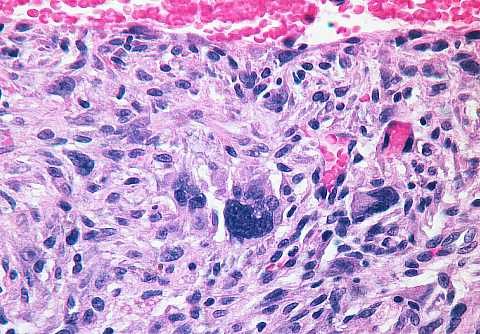

High power view in the vicinity of the black line. The characteristic of the pushing border should be assessed on the scan power image since infiltration is seen in the high power view: